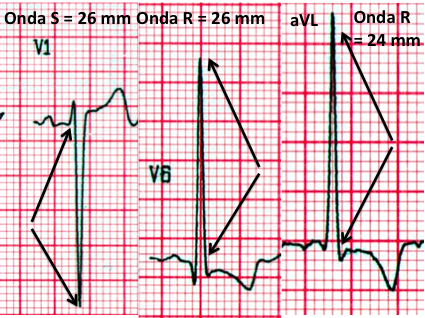

Exemplo prático de como calcular:

Neste caso, somando-se a onda S de V1 (26 mm) com a onda R de V6 (26 mm) temos 52 mm, bastante superior aos 35 mm propostos por Sokolow e Lyon.

Mas e a derivação aVL colocada no canto direito da figura acima? Pois é. Este é o outro critério famoso de Maurice Sokolow. Onda R em aVL com amplitude superior a 11 mm = SVE.